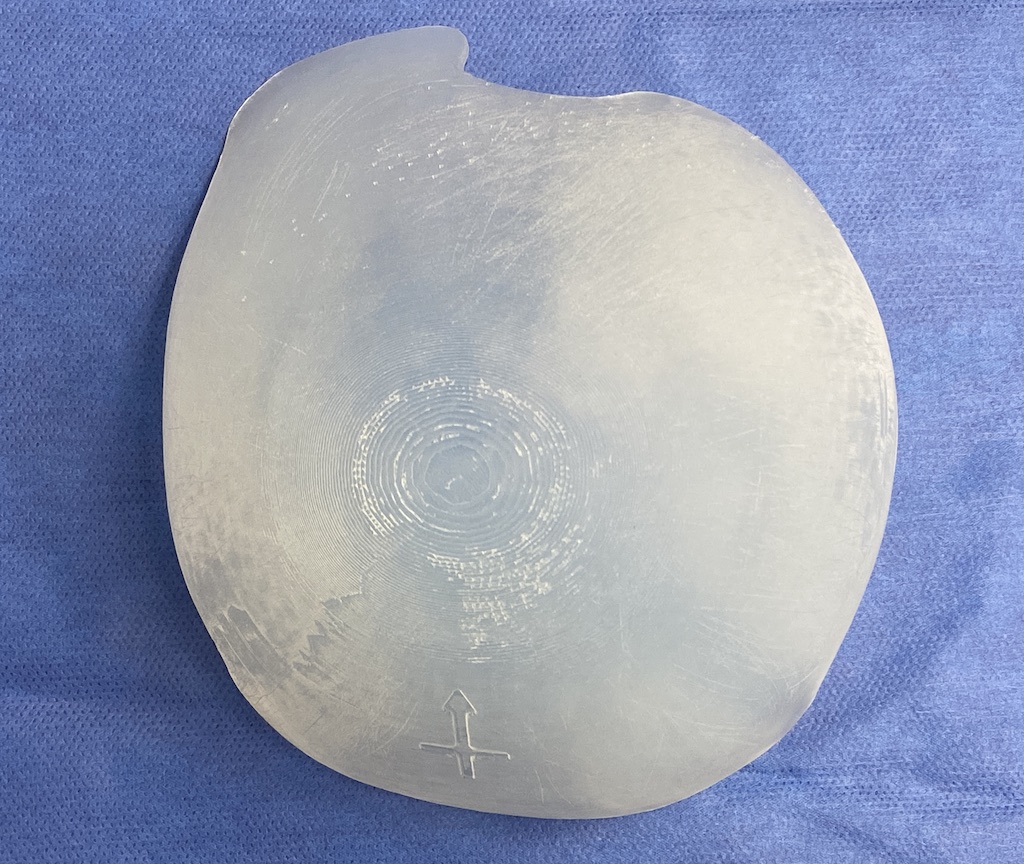

Desire for an improved head shape so that it looks rounder and not so peaked or sloped.

Placement of custom skull implant for parasagittal augmentation to create a rounder head shape. An example of what appears to be a high sagittal crest that is really low parasagittal skull areas.

Desire for an improved head shape so that it looks rounder and not so peaked or sloped.

Placement of custom skull implant for parasagittal augmentation to create a rounder head shape. An example of what appears to be a high sagittal crest that is really low parasagittal skull areas.